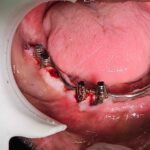

C1005 zygomatic basal implant full mouth – Ali Hasan 4

Dr. N.B. Singh